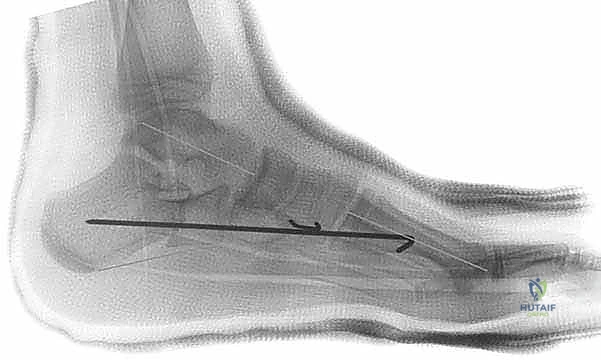

3. القطع العظمي (The Osteotomy)

باستخدام منشار جراحي دقيق، يتم إجراء قطع في عظم الكعب (Calcaneus). يتم تحديد مكان القطع بدقة بالغة، عادةً على بعد حوالي 1.5 سم خلف المفصل العقبي النردي (Calcaneocuboid Joint). يحرص الدكتور هطيف على الحفاظ على القشرة العظمية الداخلية (Medial Cortex) سليمة لتكون بمثابة مفصلة (Hinge) تمنع عدم استقرار العظم.

4. المباعدة وإدخال الطعم العظمي (Distraction and Grafting)

يتم إدخال أداة مباعدة خاصة (Lamina Spreader) في شق القطع العظمي لفتحه تدريجيًا. أثناء هذا الفتح، يراقب الدكتور هطيف استجابة القدم؛ حيث يلاحظ ارتفاع القوس الطولي وتصحيح انحراف الكعب في الوقت الفعلي.

بمجرد الوصول إلى التصحيح المثالي، يتم قياس الفجوة بدقة وإدخال طعم عظمي (Bone Graft) مناسب الحجم (غالباً ما يكون على شكل إسفين Wedge). يمكن أن يكون الطعم مأخوذًا من حوض المريض (Autograft) أو طعمًا عظميًا صناعيًا أو من بنك العظام (Allograft).

5. التثبيت الداخلي (Internal Fixation)

لضمان عدم تحرك الطعم العظمي أثناء فترة الالتئام، يتم تثبيت التكوين الجديد. يستخدم الدكتور هطيف أحدث تقنيات التثبيت، والتي قد تشمل شريحة معدنية صغيرة مع مسامير (Plate and Screws)، أو مسامير معدنية تمر عبر العظم، أو أسلاك كيرشنر (K-wires)، وذلك لضمان أقصى درجات الثبات الميكانيكي.

يتم التأكد من صحة التثبيت والتصحيح باستخدام جهاز الأشعة السينية المباشر (C-arm Fluoroscopy) داخل غرفة العمليات قبل إغلاق الجرح.